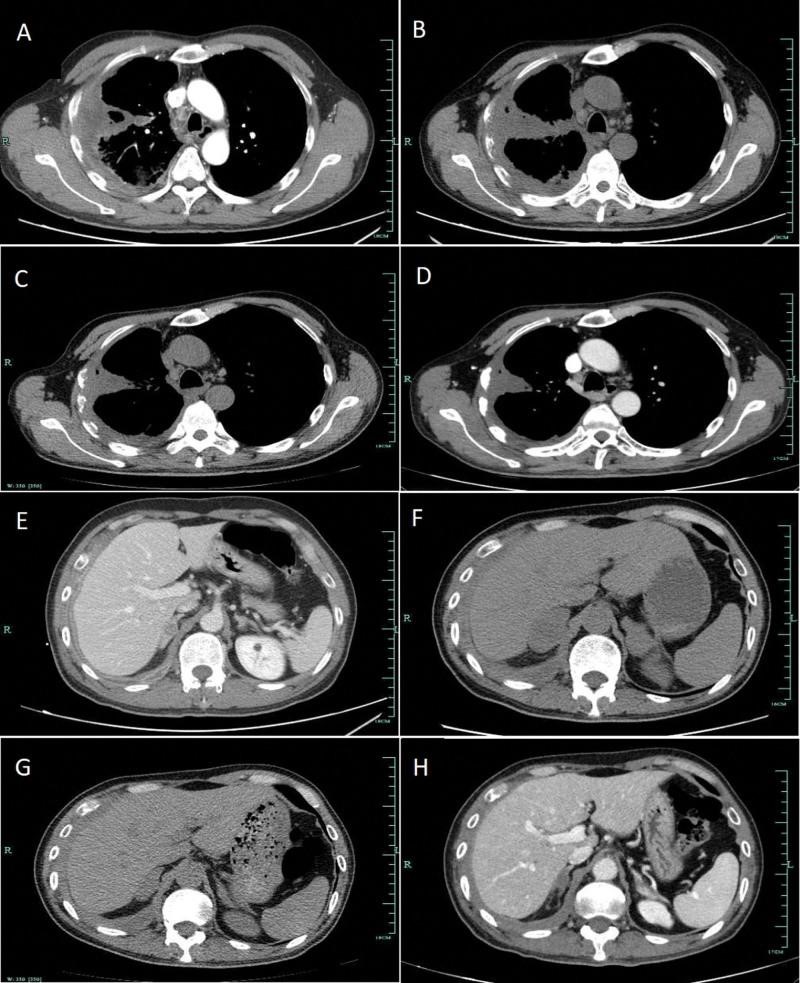

埃克替尼于2019年11月12日作为一线靶向治疗给药。此外,患者接受了右侧肩胛骨的姑息性放疗。两个月后,胸部CT显示肺部肿块无明显变化,胸膜增厚,淋巴结肿大,但双侧肾上腺转移灶有明显进展。采用患者血浆进行了包括9个基因的下一代测序基因测试,以排除共存基因突变。结果证实EGFR外显子19缺失是少有的基因突变,丰度分数为2.06%。经过2个月的靶向治疗,患者出现严重疲劳,体重减轻4公斤。然后肺癌靶向用药指导基因检测选择 pembrolizumab 单药治疗作为二线治疗,剂量为每 3 周 100 mg。服用 1 剂派姆单抗后,患者随后又接受了 4 个周期的派姆单抗治疗。根据实体瘤反应评估标准1.1版,胸部和肾上腺的病变显著减少,导致部分缓解(PR)(图3)。然而,经过 5 个周期的免疫检查点治疗后,他的腿上出现了以斑疹和丘疹为特征的皮疹,覆盖了不到 10% 的体表面积(图 4A)。根据国家综合癌症网络关于免疫检查点抑制剂相关毒性的指南,这被确定为 1 级,并在受影响的区域应用了局部类固醇。然而,他的皮肤状况继续恶化,一周后斑丘疹变得更加严重,并蔓延到他几乎所有的腿、背部和部分胸部(图 4B,C)。它现在覆盖了他身体的 30% 以上,因此被归类为 3 级。皮疹以 1 mg/kg/d 的剂量用强的松治疗。贼初,皮疹略有减少,但即使剂量加倍,药物也很快变得无效。患者随后因皮疹到另一家医院接受中药治疗,ICI治疗暂停。皮疹得到控制后,他接受了 4 个周期的紫杉醇(白蛋白结合)加顺铂化疗。2020年12月出现肝转移后再次采集血浆进行基因检测,结果仍显示除EGFR外显子19缺失突变(丰度为0.27%)外无其他致癌改变。然后,医生为他使用了埃克替尼加安罗替尼(一种口服小分子酪氨酸激酶抑制剂 VEGFR、PDGFR、FGFR、c-Kit 和 Met)。迄今为止,他已经服用了十一个月的联合靶向药物。该患者的治疗时间表如图所示图5.

图 3:EGFR-TKI 和 pembrolizumab 单药治疗期间 CT 上肺部 (AD) 和双侧肾上腺 (EH) 病变的变化。A/E:预处理。B/F:EGFR-TKI靶向治疗2个月。C/G:派姆单抗单药治疗 1 个周期。D/H:派姆单抗单药治疗 5 个周期。